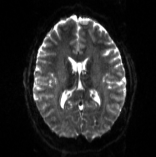

We compare the results of PyHySCO using GN-PCG, ADMM, and LBFGS on both GPU and CPU architectures. Table 3 shows the runtimes and correction quality of each optimizer on CPU and GPU. All optimizers achieve a similar correction quality with respect to relative improvement of image distance, loss value, and smoothness regularizer value, but GN-PCG has faster runtime on both CPU and GPU. On real data, GN-PCG took 10-13 seconds on average on GPU and 27-31 seconds on average on CPU, while ADMM took 11-15 seconds on GPU and 98-158 seconds on CPU, and LBFGS took 23-36 seconds on GPU and 104-141 seconds on CPU. Table 4 shows optimization metrics, including the number of iterations, stopping criteria, number of function evaluations, number of Hessian evaluations, and number of inner iterations if applicable. Consistent with its faster runtime, optimization with GN-PCG achieves a similar loss value with less computation as measured by function and Hessian evaluations. Figures 7, 8, and 9 show the field map and corrected images for each optimizer for one example subject from each dataset. The field maps and corrected images are visually similar across optimizers.

Table 6 reports the runtime and correction quality for PyHySCO using GN-PCG, HySCO, and TOPUP. On real 3T and 7T data, PyHySCO achieves lower loss and higher relative improvement between corrected images than HySCO, and higher relative improvement than TOPUP. The runtime on CPU for real data is 1-2 minutes for HySCO and over 1 hour for TOPUP, while PyHySCO on GPU has runtimes of 10-13 seconds. For the simulated dataset, PyHySCO requires an average of 1 minute on GPU, HySCO an average of 12.6 minutes on CPU, and TOPUP an average of 8.5 hours on CPU. Using the ground truth field maps from the simulated dataset, PyHySCO achieves the lowest average field map relative error, 14.48%, compared to 19.70% for HySCO and 16.36% for TOPUP. Figures 7, 8, and 9 show the field map and corrected images for one example subject from each dataset. The results of the methods are similar, and the resulting field maps are comparable to those of the existing tools, HySCO and TOPUP, while PyHySCO is considerably faster.

Refer to captionRefer to captionRefer to caption+vsubscript𝑣\mathcal{I}_{+v}inputRefer to captionRefer to captionRefer to captionPyHySCO (LBFGS)Refer to captionRefer to captionRefer to captionPyHySCO (GN)Refer to captionRefer to captionRefer to captionPyHySCO (ADMM)Refer to captionRefer to captionRefer to captionvsubscript𝑣\mathcal{I}_{-v}Refer to captionRefer to captionRefer to captionRefer to captionRefer to captionRefer to captionRefer to captionRefer to captionRefer to captionRefer to captionRefer to captionRefer to caption|+vv|subscript𝑣subscript𝑣|\mathcal{I}_{+v}-\mathcal{I}_{-v}|Refer to captionRefer to captionRefer to captionRefer to captionRefer to captionRefer to captionRefer to captionRefer to captionRefer to captionRefer to captionRefer to captionRefer to captionfield map 𝐛𝐛\mathbf{b}Refer to captionRefer to captionRefer to captionRefer to captionRefer to captionRefer to captionRefer to captionRefer to captionRefer to caption+vsubscript𝑣\mathcal{I}_{+v}TOPUPRefer to captionRefer to captionRefer to captionHySCORefer to captionRefer to captionRefer to captionvsubscript𝑣\mathcal{I}_{-v}Refer to captionRefer to captionRefer to captionRefer to captionRefer to captionRefer to caption|+vv|subscript𝑣subscript𝑣|\mathcal{I}_{+v}-\mathcal{I}_{-v}|Refer to captionRefer to captionRefer to captionRefer to captionRefer to captionRefer to captionfield map 𝐛𝐛\mathbf{b}Refer to captionRefer to captionRefer to caption